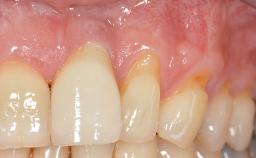

In 1983, a 51-year-old non-smoking patient was referred for the treatment of moderate chronic periodontitis. At the initial examination, 47% of sites exhibited probing depths of 4 to 6 mm. Periodontal therapy consisted of initial periodontal treatment including oral-hygiene instructions and supra- and subgingival debridement, followed by periodontal surgery to eliminate residual pockets.

| Soft Tissue Grafting | Simultaneous |